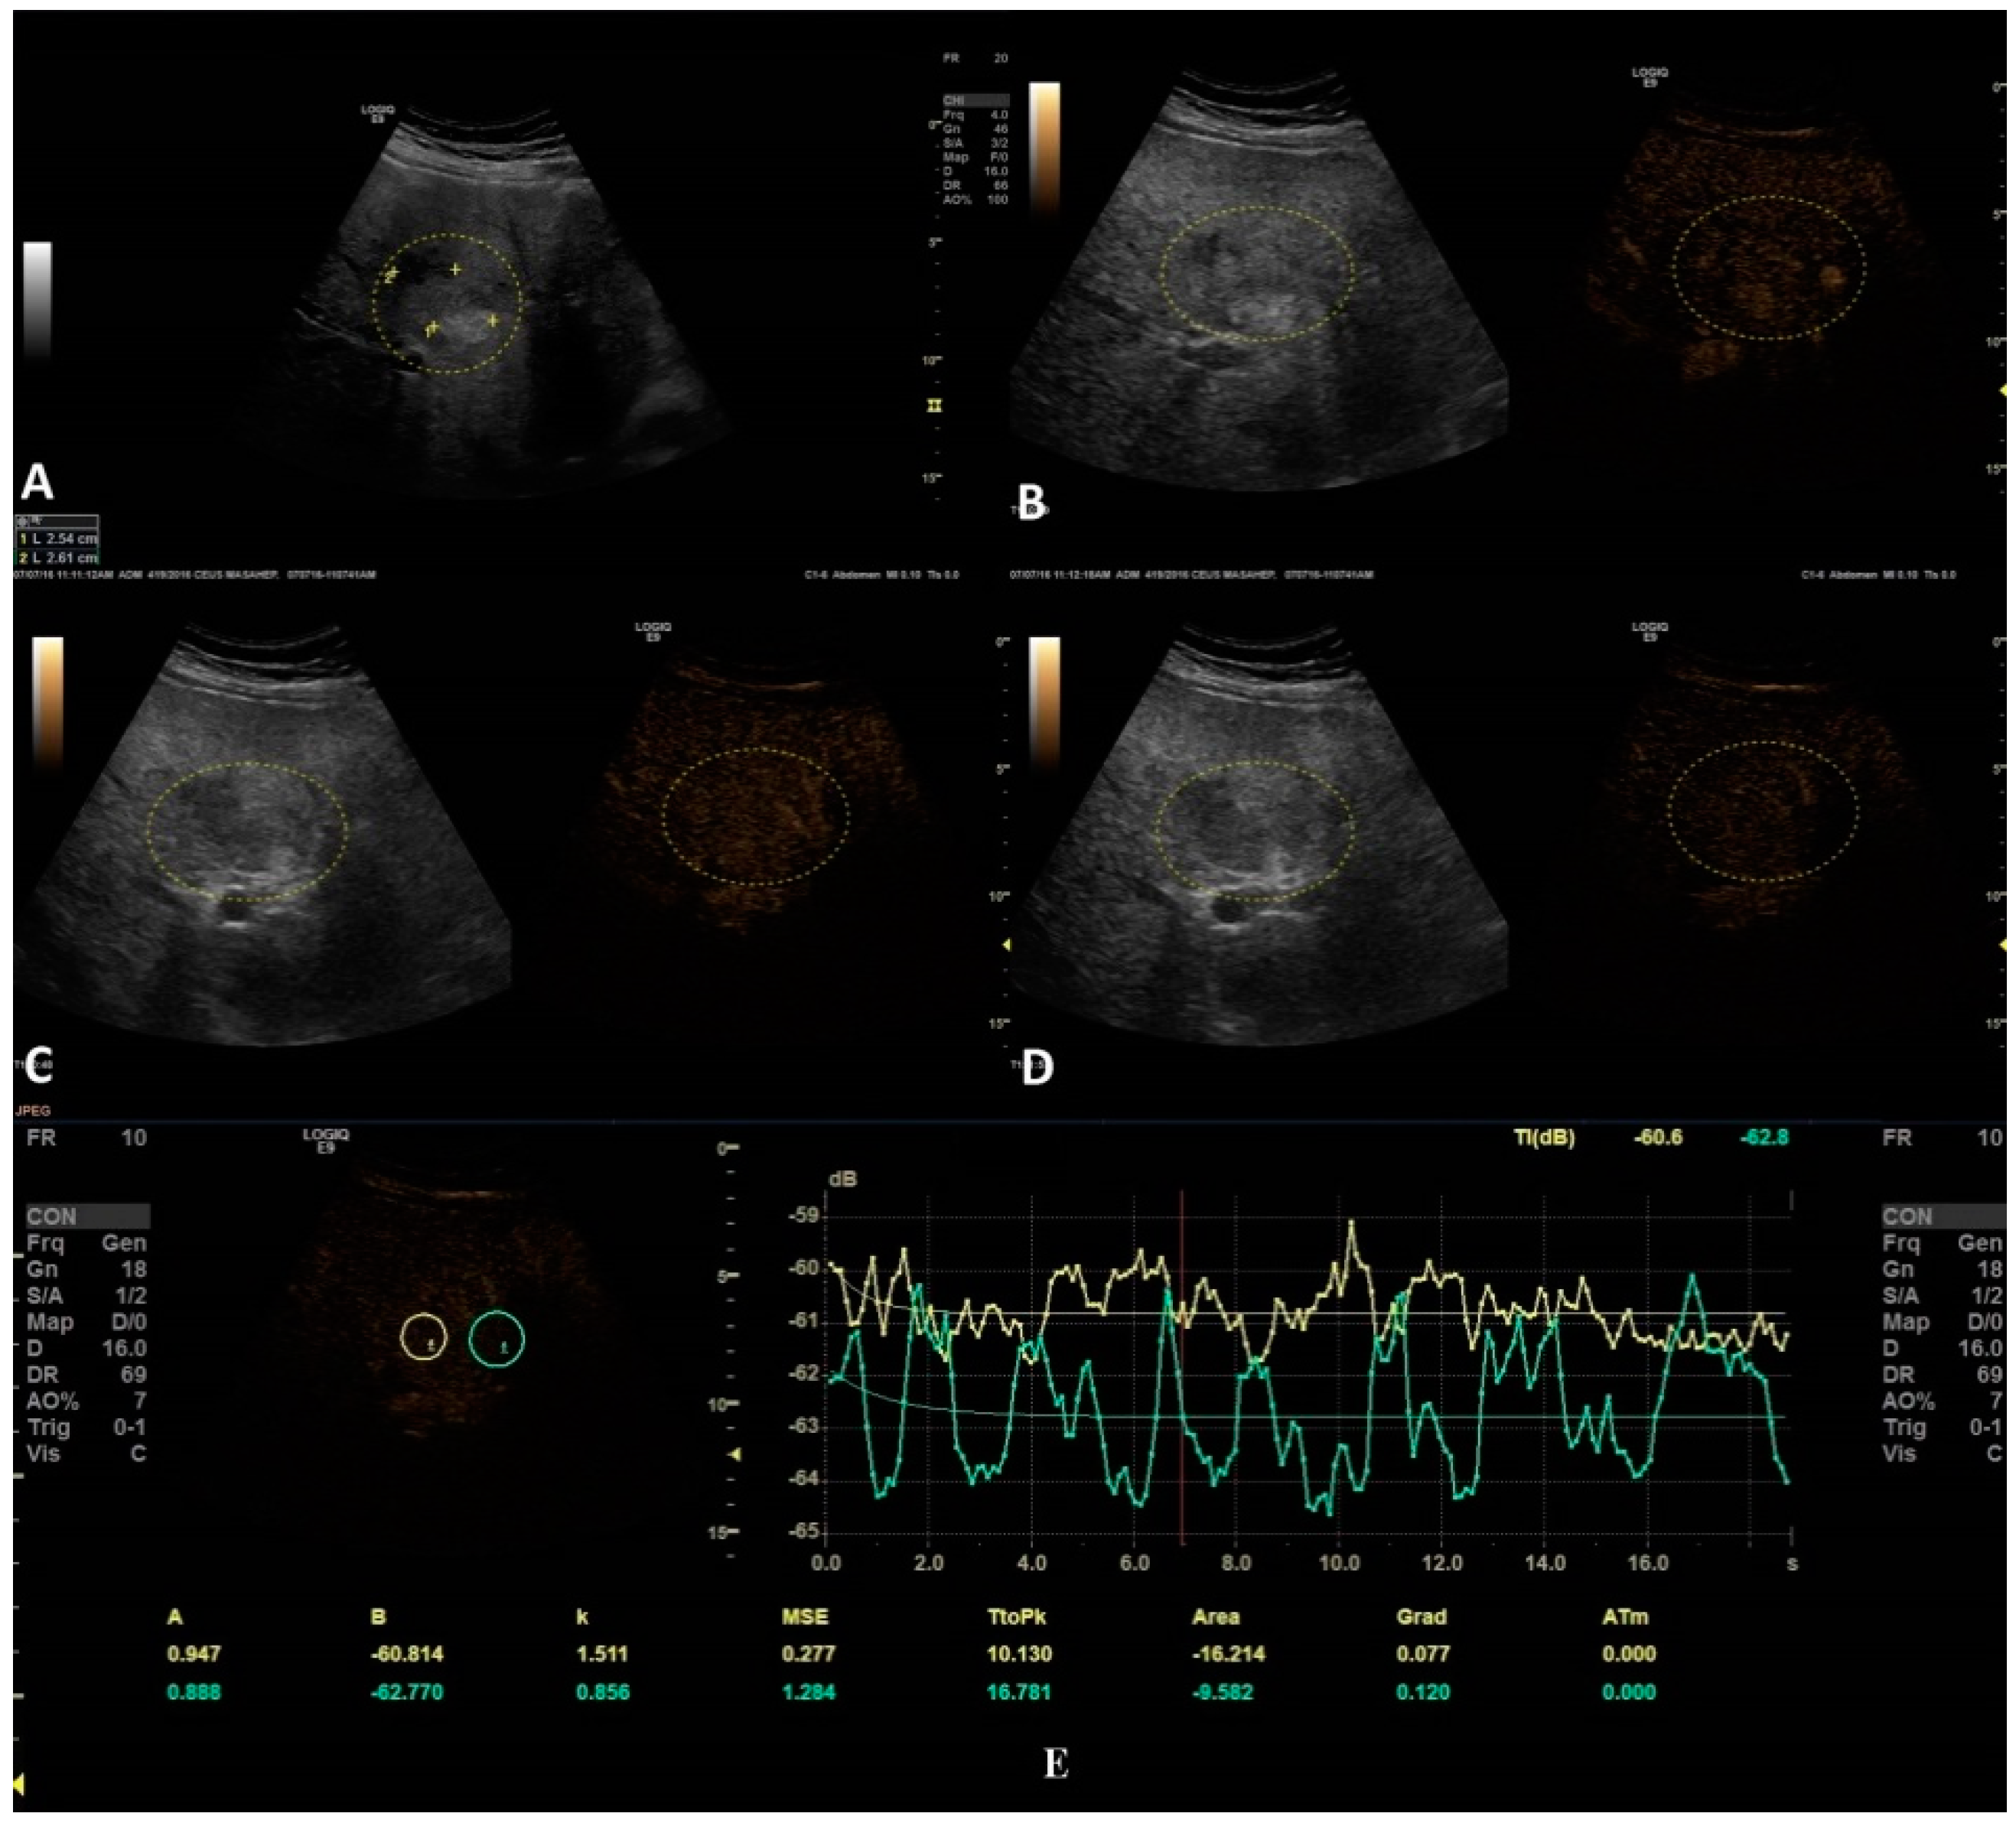

Figure 4.

In this setting, a benign lesion was assessed, as depicted in B-mode in frame (A). In frames (B–D) are depicted the vascular arterial, portal, and late phases of CEUS with different enhancement characteristics, respectively. In frame (D), the enhancement pattern is not recognizable; thus, TIC analysis (E) was applied. The results did not show us any objective washout phenomena (the graphs are not intersecting one another).